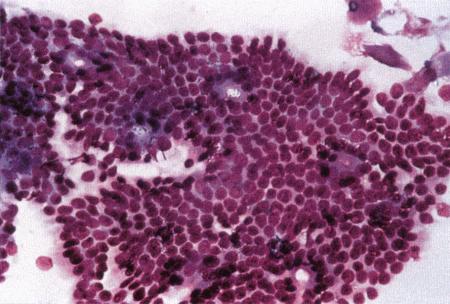

Вагинальная цитология

Повышение концентрации эстрадиола в период проэструса стимулирует деление клеток в базальных слоях вагинального эпителия, но затем концентрация эстрадиола, а соответственно и эндокринная поддержка образования нового, многослойного эпителия снижается, поэтому в образце обнаруживается больше мертвых ороговевших клеток. По мере развития проэструса снижается количество эпителиальных клеток, содержащих ядро. С начала до середины проэструса в вагинальных мазках обнаруживают повышенное содержание эритроцитов. Пик ороговения совпадает с началом повышения концентрации прогестерона; однако в начале эструса исследование не обнаруживает характерных особенностей, которые могли бы указывать на начало фертильного периода. Как правило, такой период наступает несколькими днями позже (табл. 1.1). Тем не менее вагинальная цитология остается популярным методом определения репродуктивного статуса суки из-за своей дешевизны, простоты и доступности. Для получения образца используют ватный тампон, предпочтительно небольшой, который вводят во влагалище и осторожно берут мазок. Полученные клетки помещают под микроскоп, а затем окрашивают контрастным (трихромом) или неконтрастным (например, препаратом Diff-Quik) веществом. При таком окрашивании мертвые кератинизированные клетки становятся оранжевыми, тогда как активные ядерные клетки, а также базальные и парабазальные эпителиальные клетки приобретают различные оттенки от голубого до зеленого.

Ближе к окончанию эструса вагинальные выделения претерпевают характерные изменения (снова выявляются эпителиальные клетки, содержащие ядро, и появляется большое количество лейкоцитов). Такая картина обычно наблюдается через 7–9 дней после пика ЛГ и известна как «вагинальный мазок метэструса». Изменению характера выделений предшествует переходный период, характеризующийся возрастающим количеством активных клеток и указывающий на окончание фертильного периода и эструса (табл. 1.1).

Вагинальная цитология весьма информативна в плане определения фазы эстрального цикла, однако значительные расхождения во времени появления основных признаков эструса по отношению к пику фертильности ограничивает применение указанной методики.

ВАГИНАЛЬНАЯ ЦИТОЛОГИЯ

Вагинальная цитология отражает гормональные изменения, происходящие в организме кошек (фиг. 2.2), особенно в период течки. Данный метод в племенном разведении кошек применяется реже, чем у собак, поскольку процедура может повлиять на ход цикла.

Во время фазы роста фолликулов в выделениях обнаруживаются поверхностные и кератинизированные клетки, наличие которых объясняется воздействием 17-β-эстрадиола. Процентное содержание безъядерных поверхностных клеток возрастает незначительно. В период фолликулярной фазы основной характеристикой вагинальных выделений является медленное сокращение количества клеток, содержащих ядро, промежуточных и базальных клеток. Однако указанные изменения у кошек менее выражены, чем у сук. Наиболее значимым индикатором активности эстрогена является осветление фона на предметном стекле, связанное с резким сокращением обломков разрушенных клеток и слизи. Содержание эозинофилов заметно ниже, чем у собак, эритроциты отсутствуют.

Фиг. 2.2.

Вагинальные выделения кошки (а). Выделения, типичные для фазы эструса. Большая часть клеток представляет собой безъядерные кератинизированные клетки или клетки с пикнотическим ядром. Присутствуют промежуточные клетки (b). Выделения, характерные для метэструса, — «течки», иногда наблюдаемой у кошек в конце эструса. Присутствуют поверхностные и промежуточные клетки, повышено содержание лейкоцитов. Этот короткий метэструс наблюдается в течение 24–48 часов (см. Приложение)